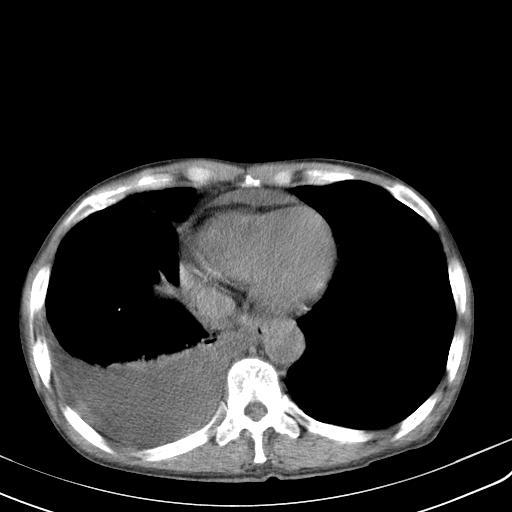

男性 75  咳嗽 一周前发热最高达39

右肺继发型tb并右侧tb性胸腔炎,右侧胸腔大量积液并右下肺膨胀不全,慢支肺气肿、多发肺大泡。建议抽胸水实验室检查并复查排除恶性在占位。

右上肺继发型肺结核,右胸腔中等量积液。

结核的基础上有纵隔淋巴结肿大,右侧有胸水,但右侧纵隔反而窄,说明有肺有不张。

再就是右下肺有块影,和不张混合,还是不能除外肺癌。

补充材料,患者2月份ct片大致正常,双侧胸腔积液,2月份抽胸水未发现ca细胞,现患者发热,痰多,各气管通畅,

1)右肺继发型肺结核。2)左肺胸膜下多发性肺大泡。3)右侧胸腔积液。